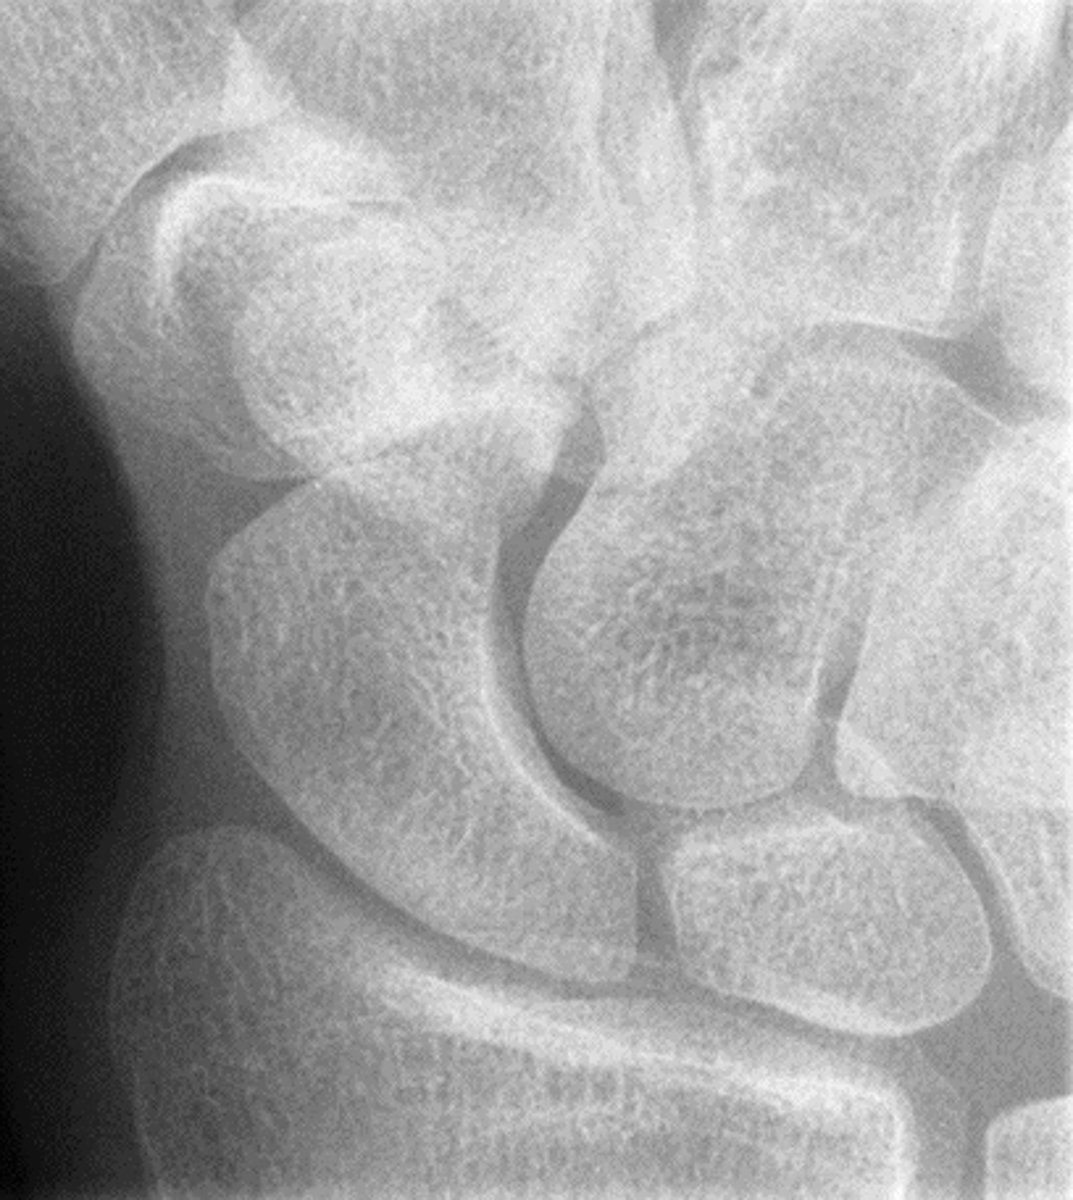

PA Wrist

PA Oblique Wrist

Tangential inferior superior carpal canal hand